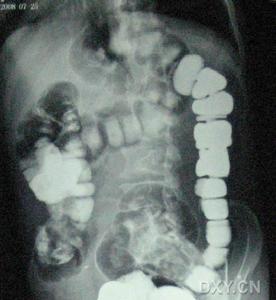

2.X線

X線腹部平片及側位片比較觀察兩側腹膜脂肪線、兩側腰大肌陰影及脊椎等情況。可發現軟組織腫塊、腎輪廓清清、腰大肌外形改變等。